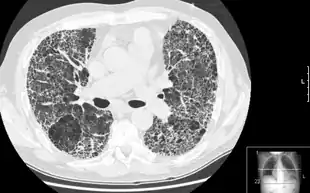

HRCT of lung showing extensive fibrosis possibly from usual interstitial pneumonitis. There is also a large emphysematous bulla.

HRCT is used for diagnosis and assessment of interstitial lung disease, such as pulmonary fibrosis, and other generalized lung diseases such as emphysema and bronchiectasis.

HRCT may be diagnostic for conditions such as emphysema or bronchiectasis. While HRCT may be able to identify pulmonary fibrosis, it may not always be able to further categorize the fibrosis to a specific pathological type (e.g., non-specific interstitial pneumonitis or desquamative interstitial pneumonitis). The major exception is UIP, which has very characteristic features, and may be confidently diagnosed on HRCT alone.[9]